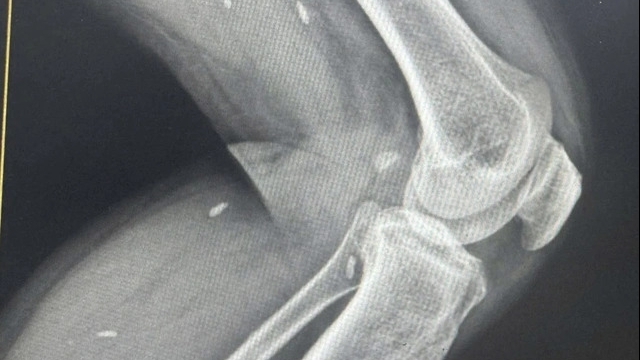

![]() |

| Ảnh minh hoạ |